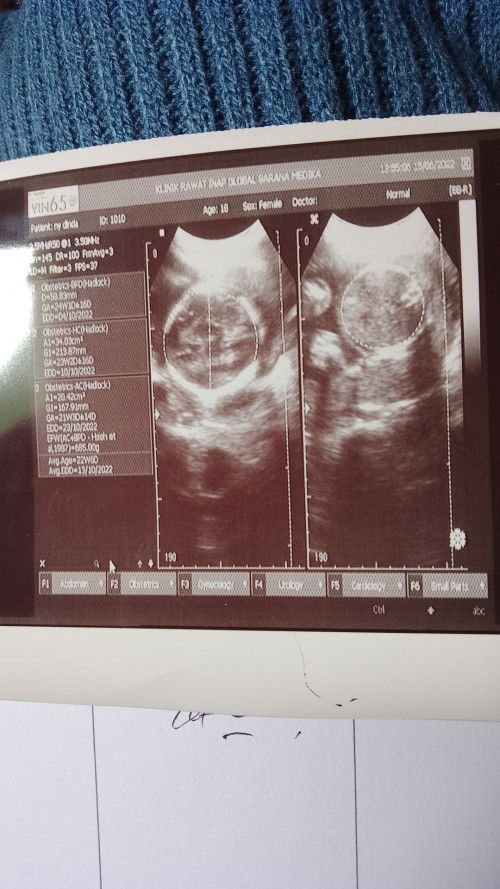

Bun itu usia kehamilan nya yang mana yaπŸ™πŸ»

Usg #seriusnanya

GA itu usia kehamilan bu

samping kiri di kotak keterangan, paling bawah ada Avg GA kan, ya itu usianya